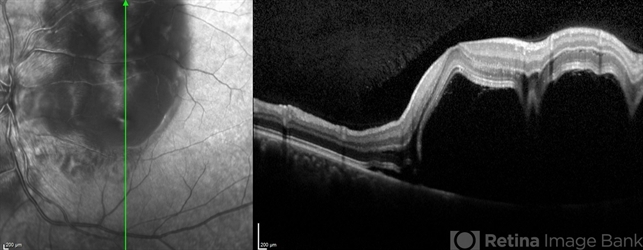

- Preeclampsia in a 30 YO

- preeclampsia, central scotoma, blurred vision

- Optical coherence tomography system

- A 30-year-old presented with central scotoma and blurred vision a day following C section for preeclampsia